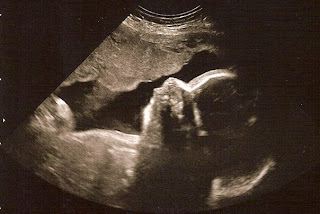

I had my 31 week appointment or if you want to get technical, 30wks 6 days. We got a little sneak peek at our little 2.0 and even got a cool 3d/4d pic just like we did with Elias. Appt went really well for both baby and Momma. My blood pressure is good and his heart rate is awesome. I have only gained 4lbs so far so they were a little concerned about that but baby seems to be measuring right on track.

| cute little profile |